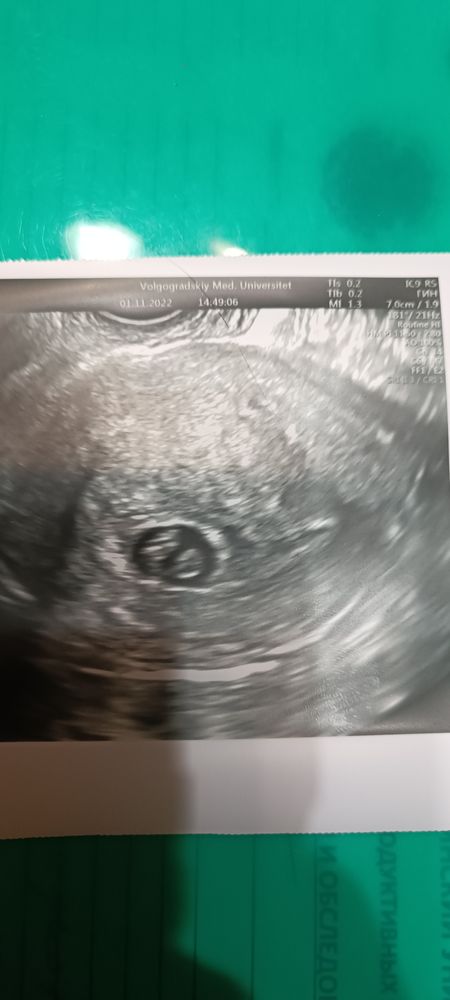

УЗИ 7 недель

Меня смущает размер плодного яйца, очень маленькое для срока и для такого ктр,там места почти нет

Марина, мне теперь и на снимке кажется что места мало Изображение

Елена, похоже что да( пя маленькое

Может ошиблись в измерении пя, так-то все не плохо,кроме пя,я посмотрела ваше УЗИ,которое было сделано 15 дней назад,там пя было 6,3 мм,за 15 дней выросло всего на 6 мм,это прям совсем мало,в норме по 1 мм в день растет,вы хгч не сдавали? От роста хгч напрямую зависит размер плодного яйца и его рост